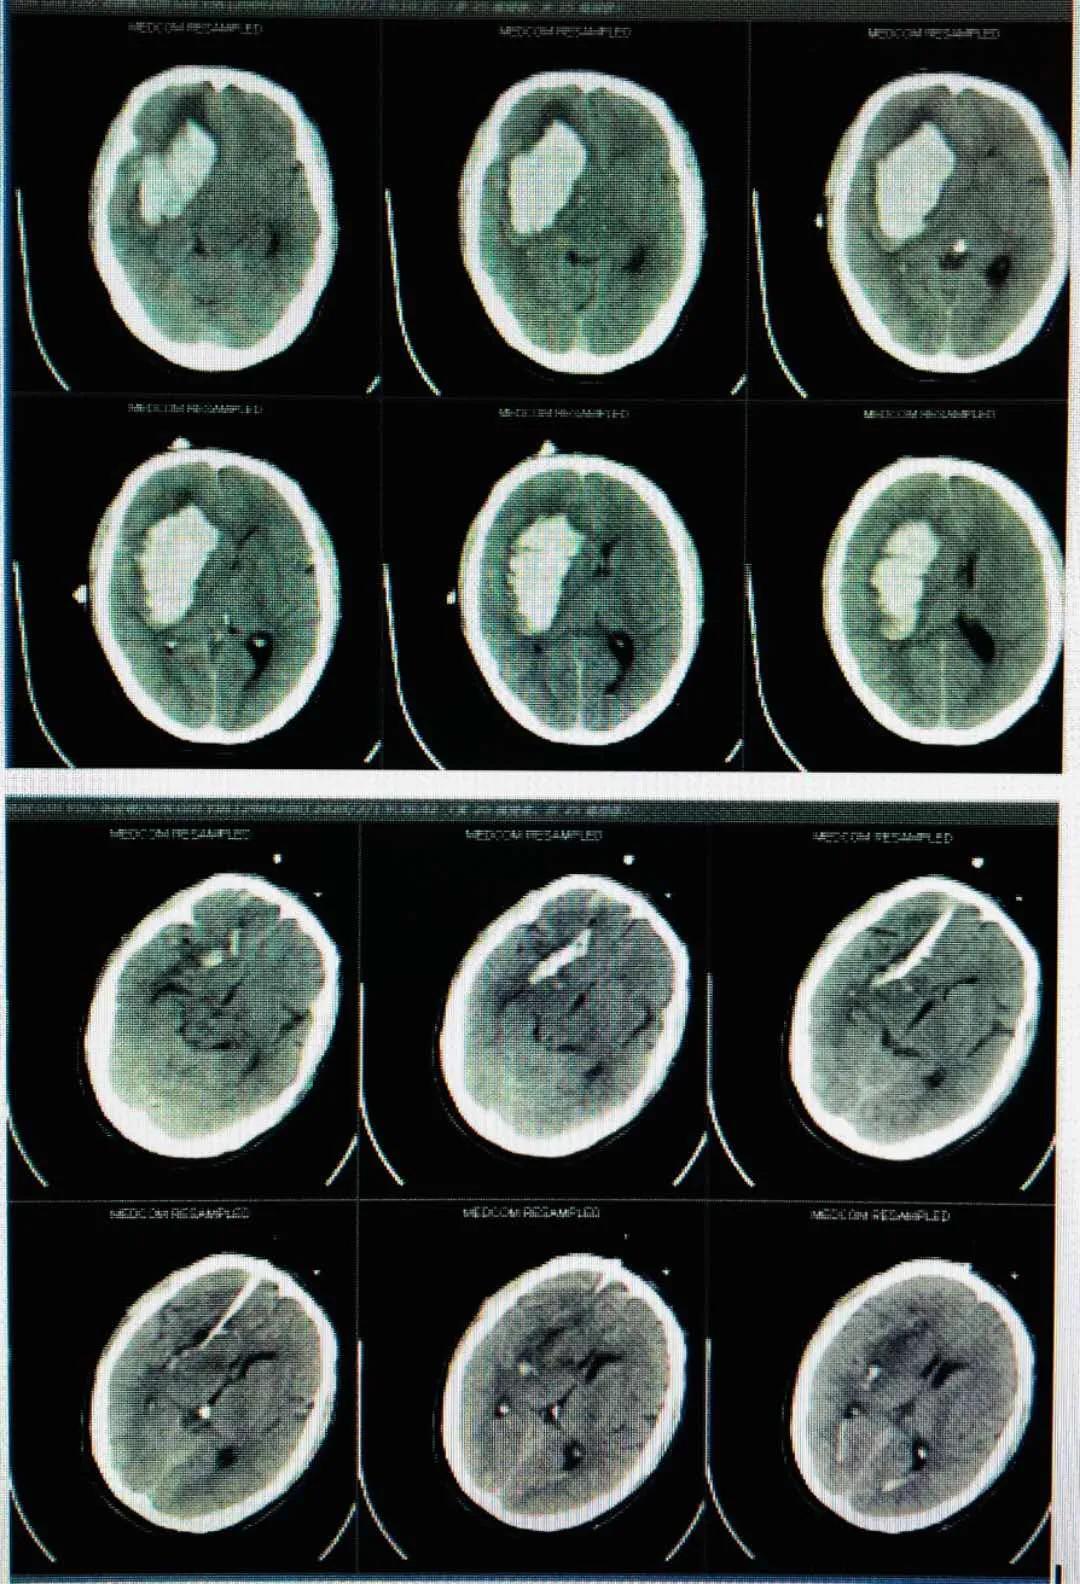

患者高某,男性,73岁,于入院2个半月前因外伤致伤头部,当即人事不省,无口吐白沫、双眼上吊、四肢抽搐,无大、小便*禁失**等不适,经福建医科大学附属第一医院治疗后好转。1个月前就诊我院康复科,行康复治疗。半个月前患者开始出现精神态势欠佳,呈痴呆状,意识障碍,大、小便*禁失**。诊断为创伤性脑积水、左侧额部硬膜下积液、右侧颞叶软化灶、两肺下叶炎症。5月18日在局部麻醉下行“脑室腹腔分流术”。

术后,给予预防感染和抗癫痫等对症支持处理,患者病情慢慢恢复。